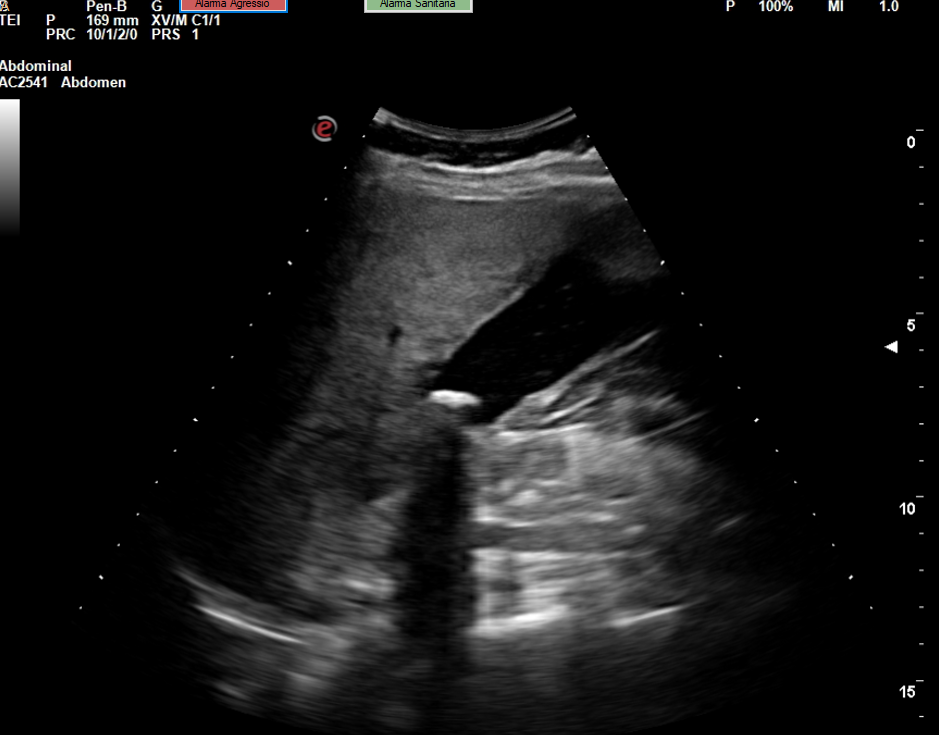

Descripción de los hallazgos ecográficos y las imágenes más relevantes para la resolución del caso

Se realiza la ecografía abdominal en el ambulatorio, donde se objetiva colelitiasis con el colédoco en el límite superior de la normalidad (4,4 mm), también presenta esteatosis hepática grado I. El resto de la ecografía no presenta hallazgos de interés.